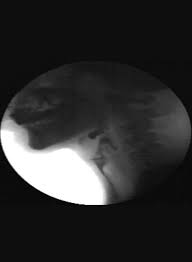

Barium swallow definition x ray. Fluoroscopy is often used during a barium swallow test. This series looks at your esophagus stomach and the first part of the small intestine duodenum. The progress of the barium is followed radiographically to detect filling defects e g places where a normal outline of barium should be seen. A test that involves filling the esophagus stomach and small intestines with a barium solution in preparation for an x ray to define the anatomy of the upper digestive tract.

Barium sulfate is a metallic compound that shows up on x rays and is used to help see abnormalities in the esophagus and stomach. A barium swallow is a test that may be used to determine the cause of painful swallowing difficulty with swallowing abdominal pain bloodstained vomit or unexplained weight loss. Upper gi barium swallow choose which type of a calculation. When taking the test you drink a preparation containing this solution.

Fluoroscopy is a kind of x ray movie why is a swallow test done. A barium swallow is a special type of x ray test that helps your doctor take a close look at the back of your mouth and throat known as the pharynx and the tube that extends from the back of the.